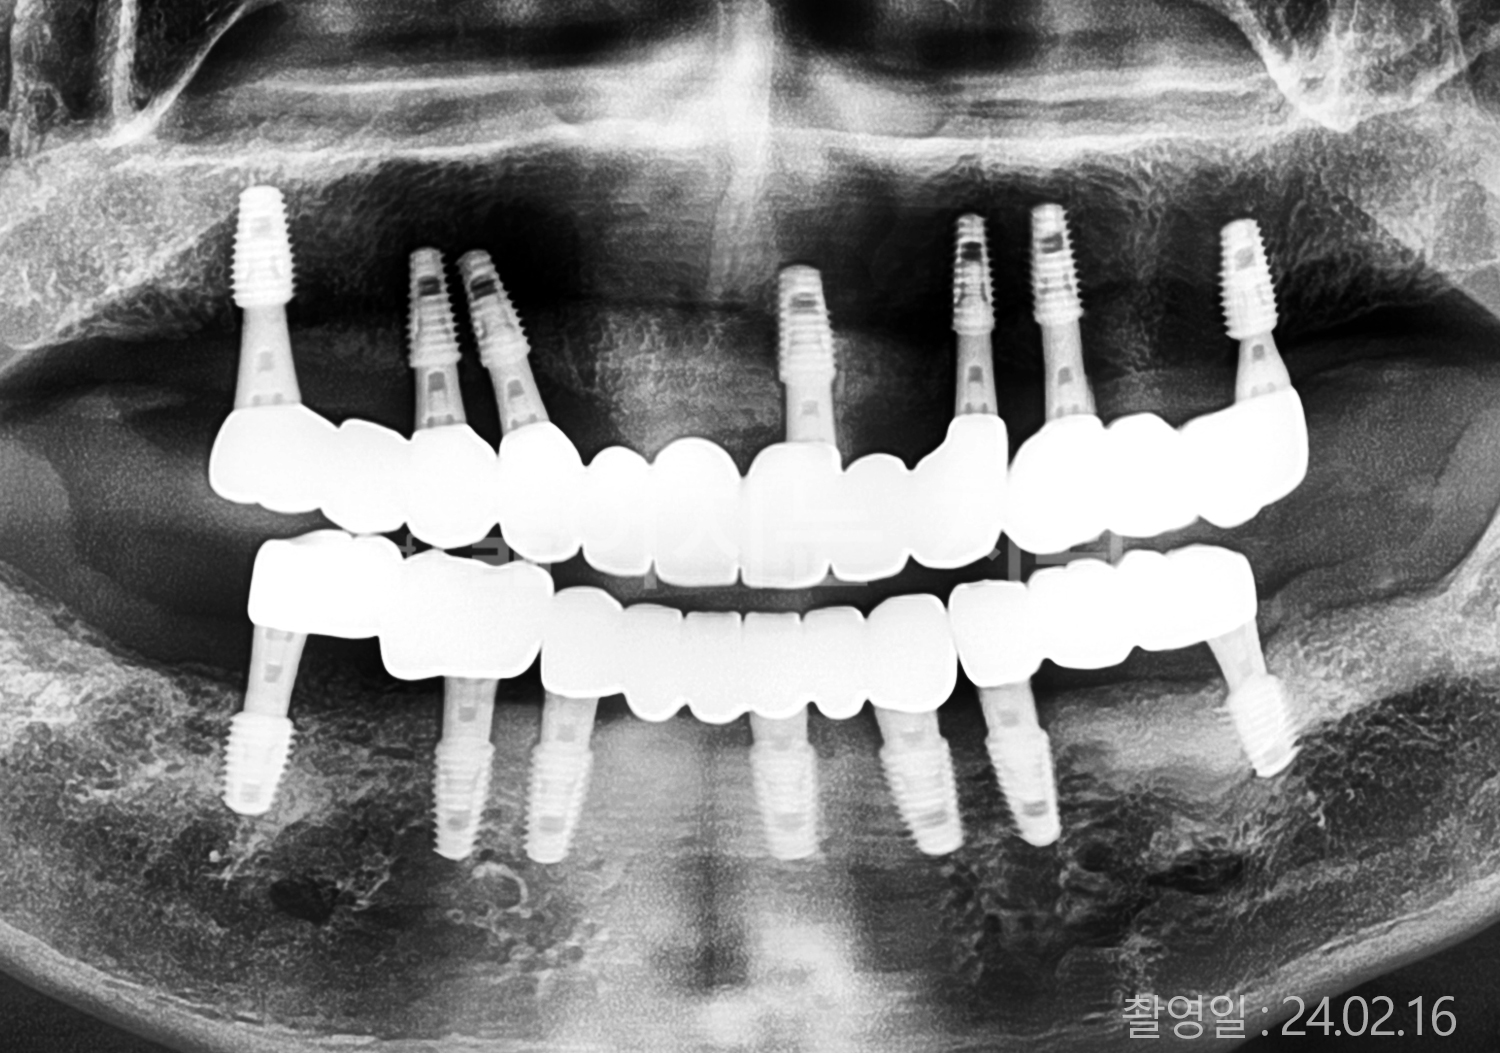

• 60대 고혈압, 고지혈증 전체치아 10개 이상 임플란트

• 70대 전체치아 10개 이상 임플란트

• 60대 전체치아 10개 이상 임플란트

• 50대 전체치아 10개 이상 임플란트

• 50대 고혈압, 고지혈증 전체치아 10개 이상 임플란트

• 60대 고혈압, 당뇨, 고지혈증 전체치아 10개 이상 임플란트

• 80대 고혈압, 당뇨, 골다공증 전체치아 10개 이상 임플란트

• 60대 고혈압 전체치아 10개 이상 임플란트

• 60대 고지혈증 전체치아 10개 이상 임플란트

• 60대 당뇨 전체치아 10개 이상 임플란트